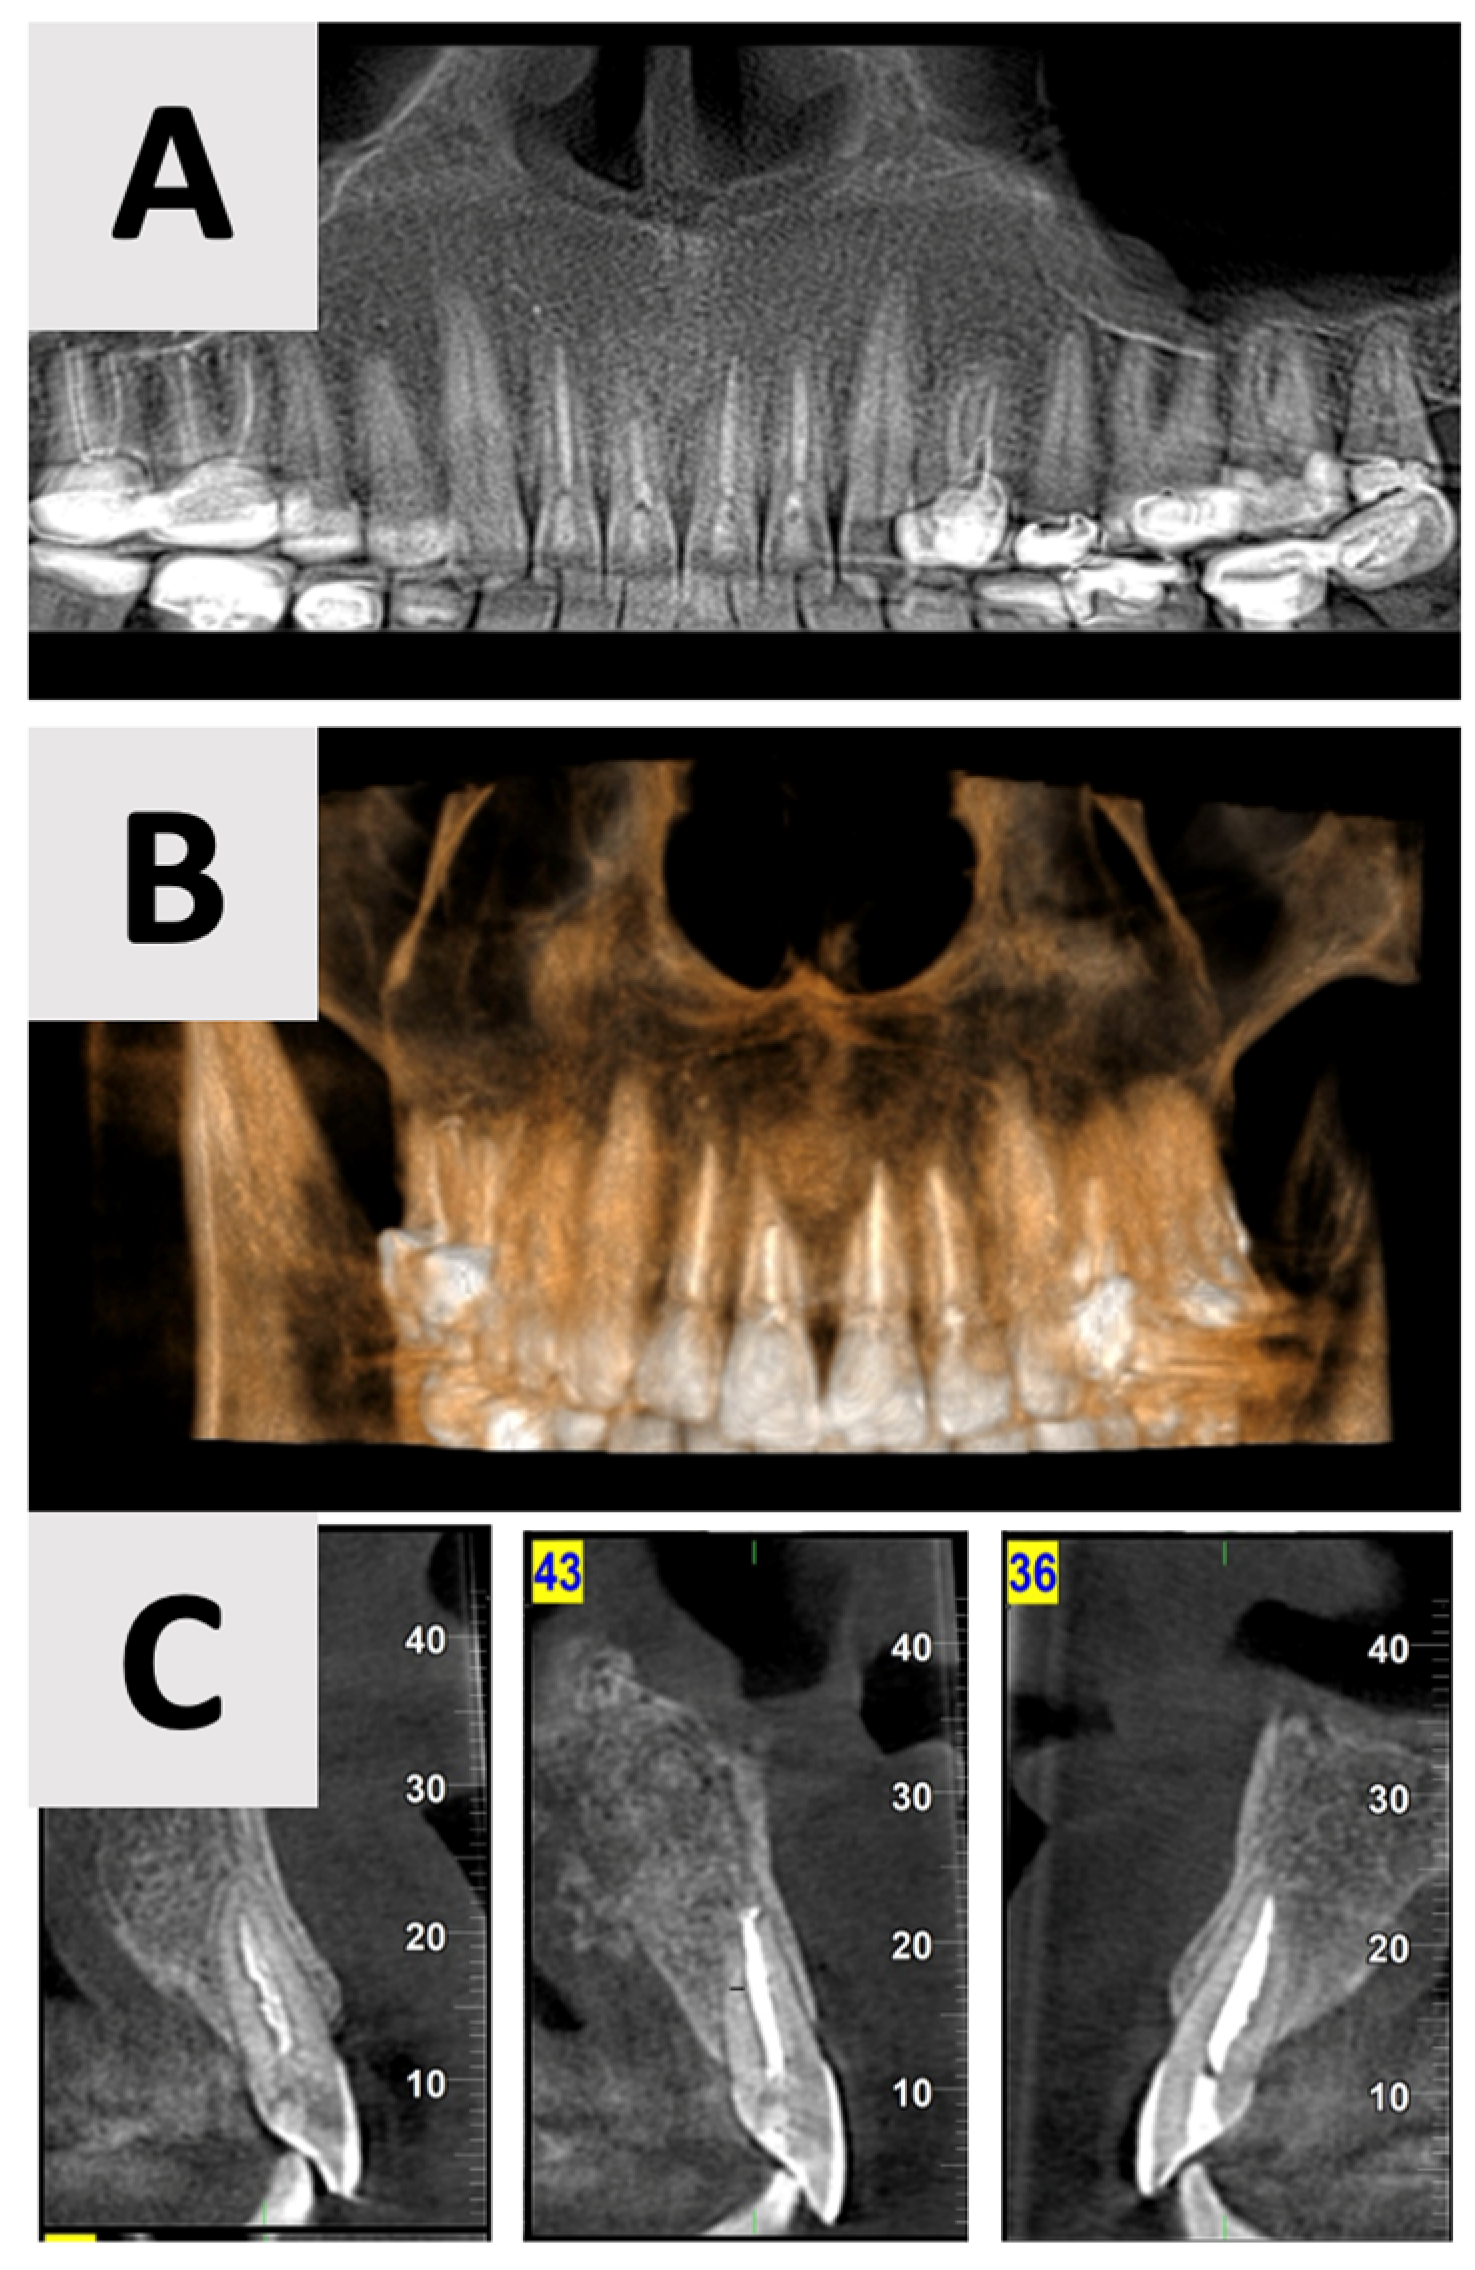

Cone Beam Computed Tomography (CBCT) was performed using the NewTom GO 2D/3D® system (NewTom, Verona, Italy). Imaging was performed to assess the extent and characteristics of the lesion (Figure 1). The CBCT revealed a unilocular hypodense area palatal to the anterior four maxillary teeth, absence of palatal bony walls and intact buccal bony frame. Lesion dimensions were 17 mm (mesiodistal) × 15 mm (buccolingual) × 21 mm (height). These radiographic findings are consistent with the characteristics of a radicular cyst, which typically presents as a well-defined, unilocular radiolucency associated with the apex of a non-vital tooth. The absence of palatal bony walls suggests potential expansion or erosion of the palatal cortex.

Figure 1.

Radiographic images of the cyst at initial visit before marsupialization. (A) Axial, and (B) coronal views of the cyst center. Measurements indicate cyst dimensions: mesiodistal 17 mm × buccolingual 15 mm × height 21 mm.